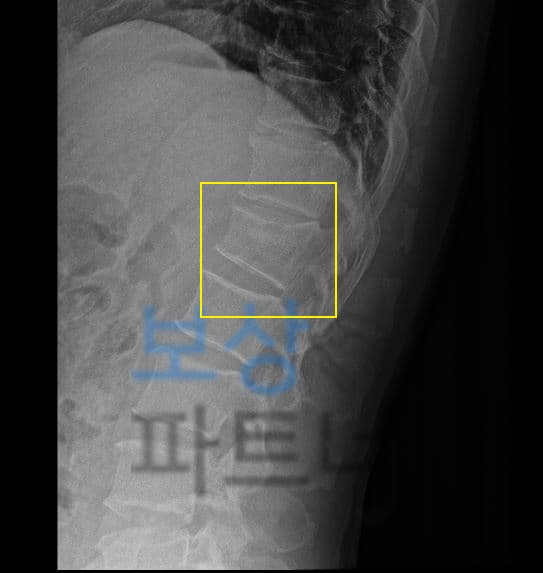

흔히 척추 1번 이라고 생각하시는 요추의 1번 골절 진단 받으셨습니다. 특히 요추1번 부위는 척추 골절 시 가장 빈번하게 발생하는 부위 중 하나인데요, 본래 자연스러운 S만곡을 형성하는 척추의 흉추와 요추가 교차하는 부위로서 추락사고, 낙상사고, 미끄러짐 사고에 금이가고 골절되는 사고가 많이 일어납니다.

요추1번 골절된 김@@님은 다행히 골밀도도 나쁘지 않아 보존적 치료로 TLSO 보조기 착용하며 3개월 정도 침상안정을 취하셔야 했는데요, 이러한 상황에 내가 가입해둔 보험에서 내가 가입한 보험에서 후유장해 항목 찾아보세요!

AMA 방식의 후유장해 평가를 의뢰하게 되었습니다. 그 결과

의뢰인은 뚜렷한 기형 장해 30% 모두 인정받을 수 있었고